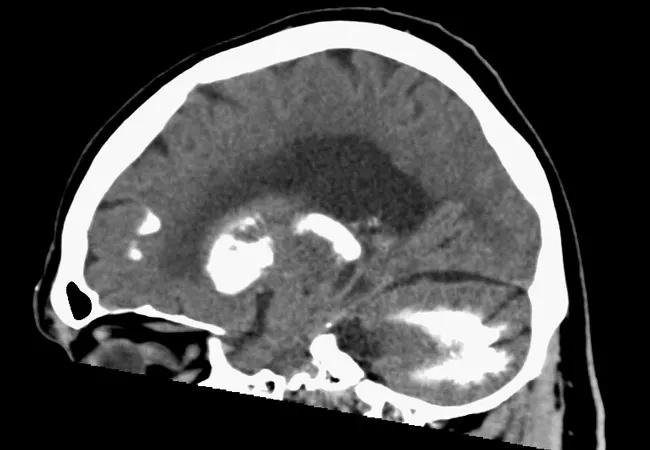

Striopallidodentate calcinosis (SPD), also known as Fahr’s syndrome, is a rare condition characterized by abnormal deposition of calcium in the brain. In a poster session during the American Geriatrics Society’s annual meeting in May 2018, Anas Souqiyyeh, MD, a fellow in Cleveland Clinic’s Department of Geriatrics, and his colleagues presented a case of a 68-year-old man with idiopathic hypoparathyroidism and hypertension who complained of short-term memory decline.

The patient reported vision deterioration and low energy, but his physical examination was normal and he denied a history of strokes or seizures. Imaging revealed extensive symmetrical calcifications in the bilateral caudate, basal ganglia, thalamus and dentate nuclei of the cerebellum. Bilateral frontal subcortical deposits were noted as well. The patient underwent neuropsychological testing, the results of which were consistent with deficits in the frontal-subcortical domains.